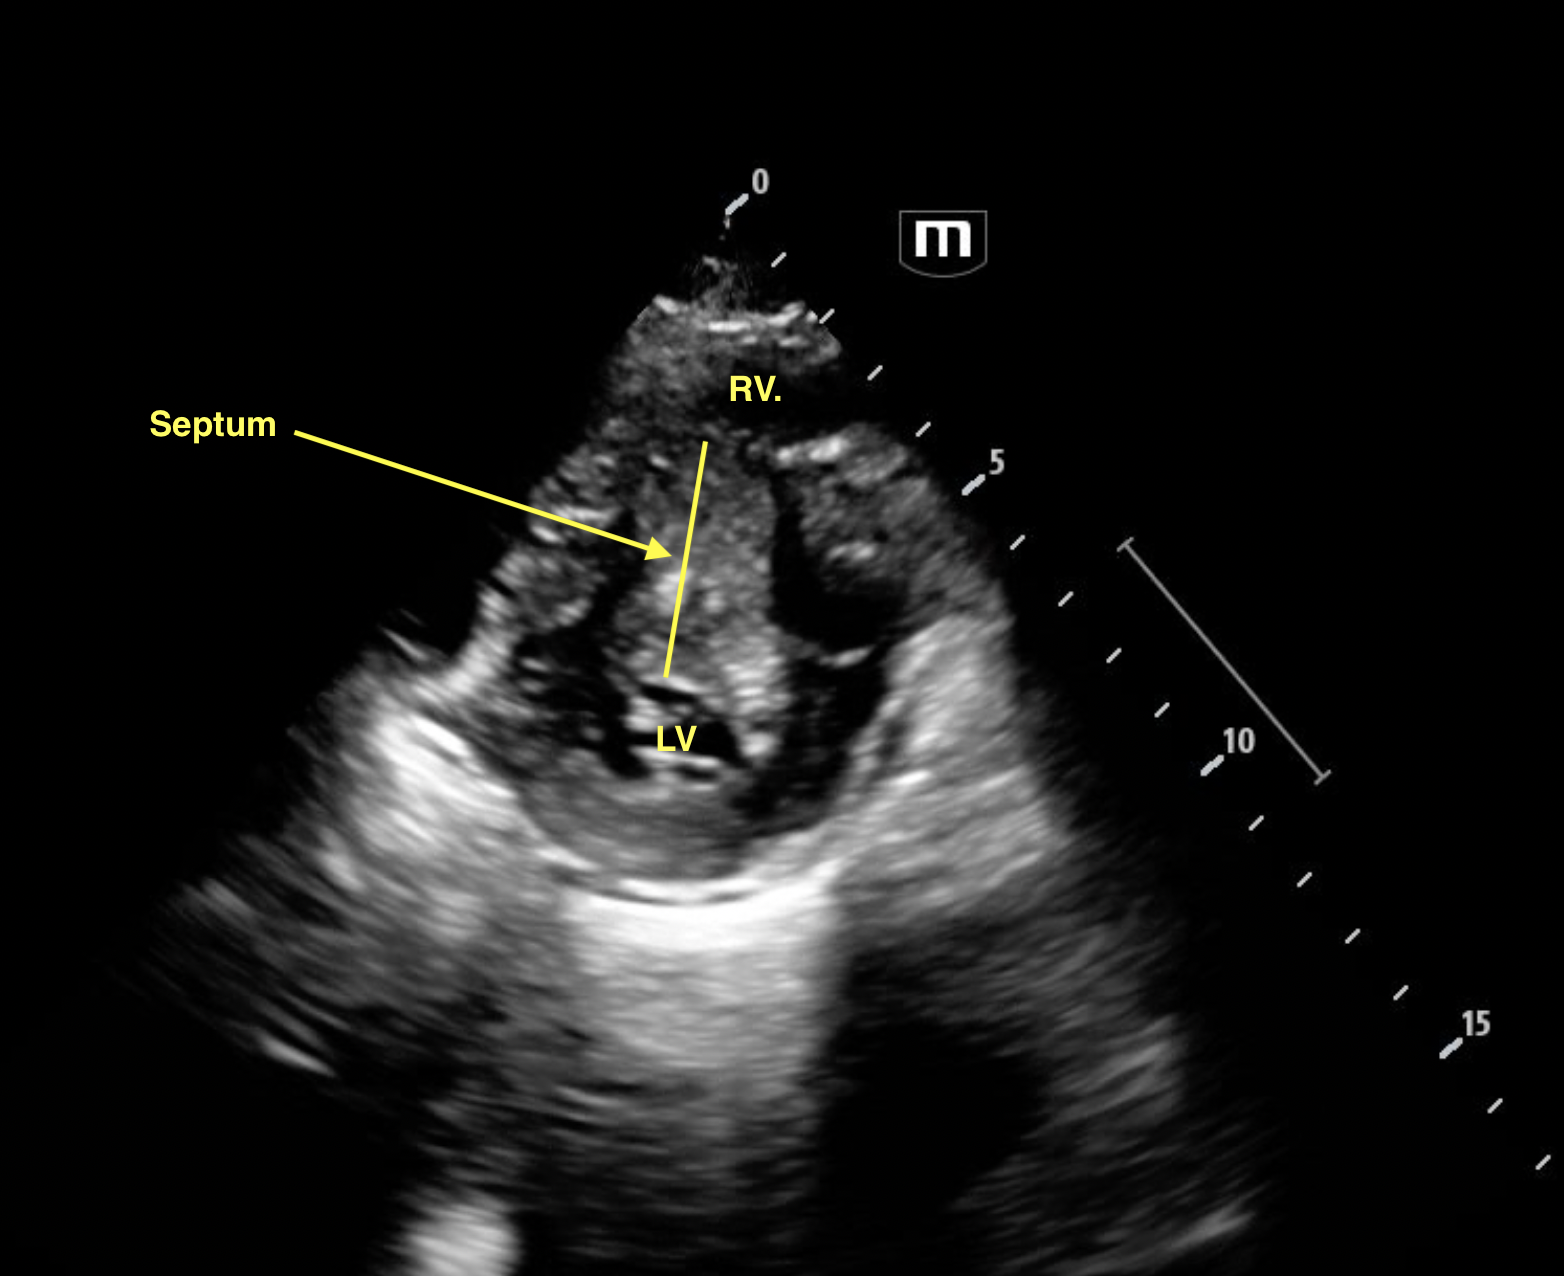

PSAx

The patient was admitted to cardiology. Formal echo revealed septal thickness of 3.2cm (normal <1cm). RV inflow was turbulent with a Vmax 4.2m/s (!!!!!!!) Mean 30mmHg and Peak Gradient of 69mmHg. For context, normal RV inflow ie flow across the tricuspid valve has a Vmax <0.7m/s.

Typically septal hypertrophy affects the LV side of the septum. But in this case, it's bulging into the RV.